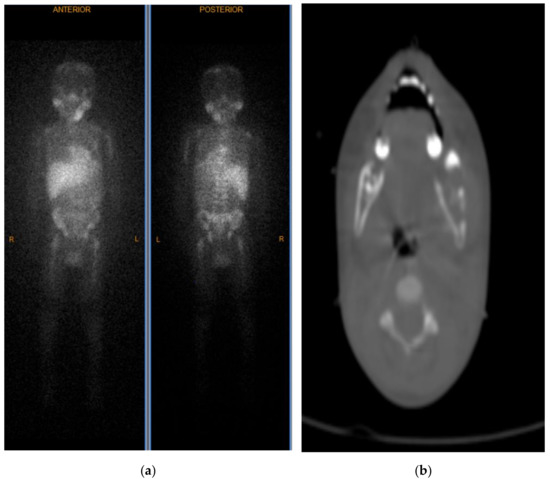

2. Case Report